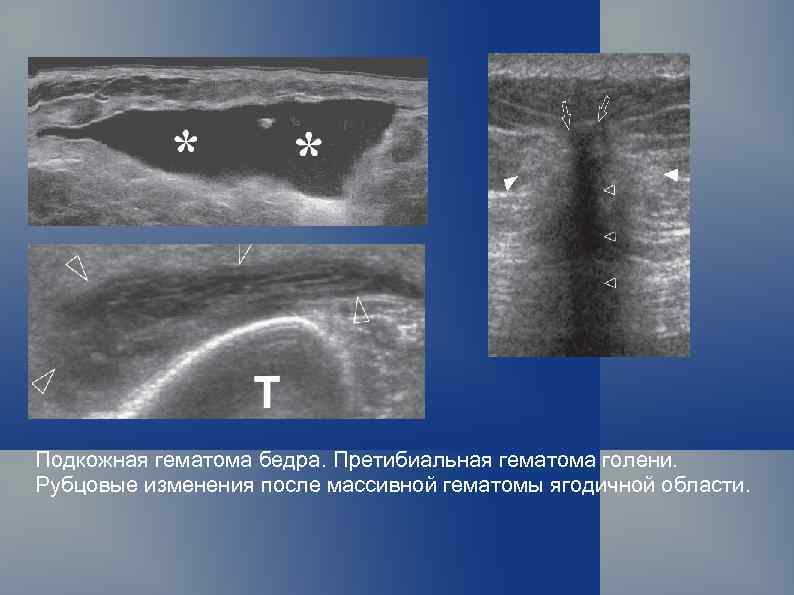

Подкожная гематома бедра. Претибиальная гематома голени. Рубцовые изменения после массивной гематомы ягодичной области.